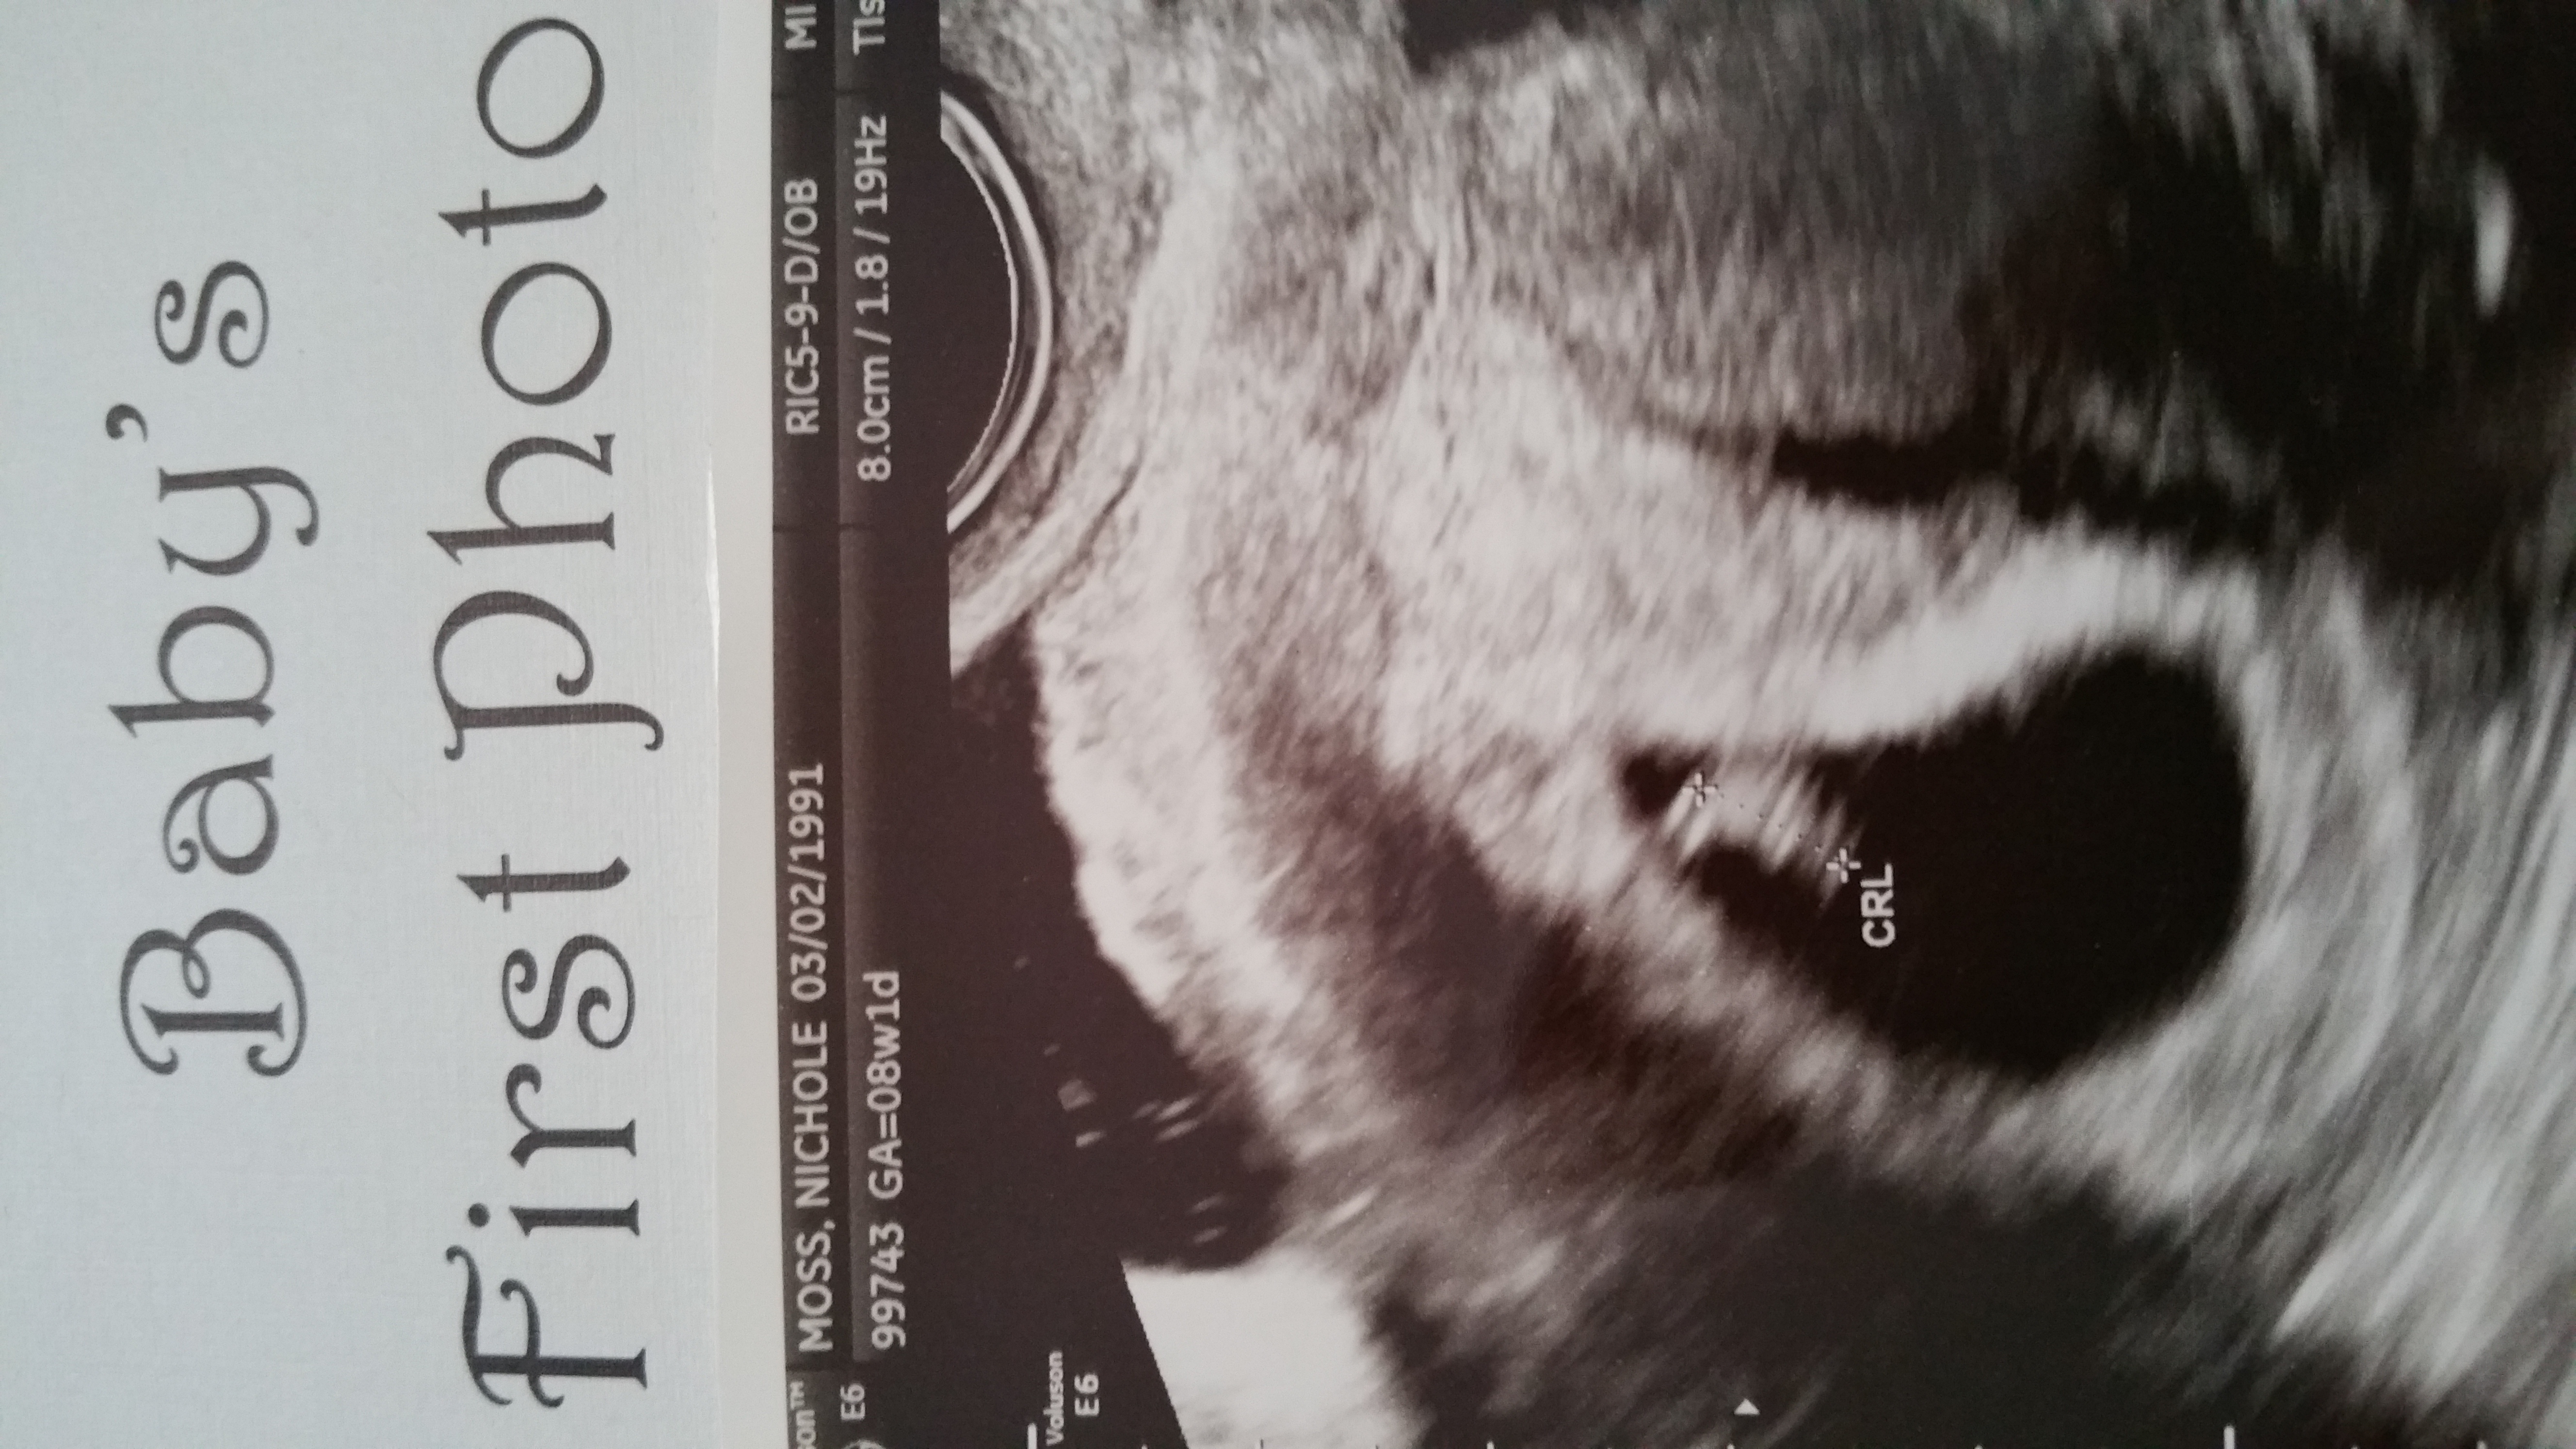

hey beautiful ladies how many of you have had your first ultrasound? How was your experience? I couldnt hold my tears when i saw the tiny being inside me with its heart beating. Such a wonderful thing to experience really:) my husband just couldnt hold smiling and looking away from the baby. Absolutely loved the experience. Here is the pic of the first ultrasound. The baby is 8 weeks 5 days as of today. Please share your experience. Would love to know